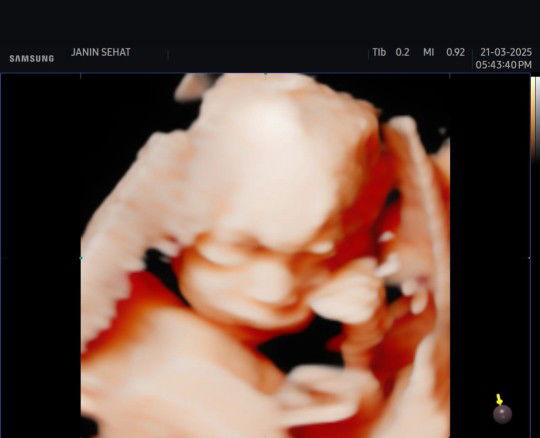

hb 10.4 di kehamilan 35 week

Menantikan saat menjadi ibu